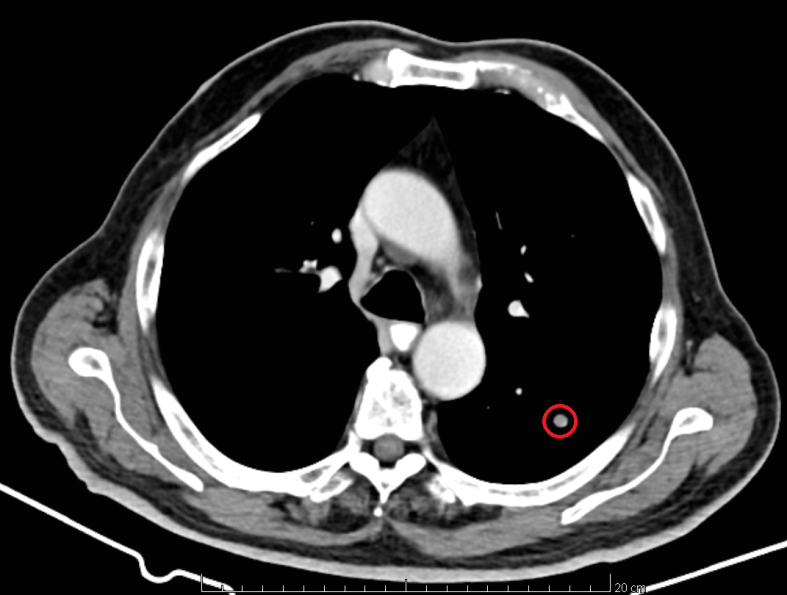

CT of the upper abdomen. Solitary metastatic focus in segment VII of the liver (Courtesy Dr. V. Penopoulos)